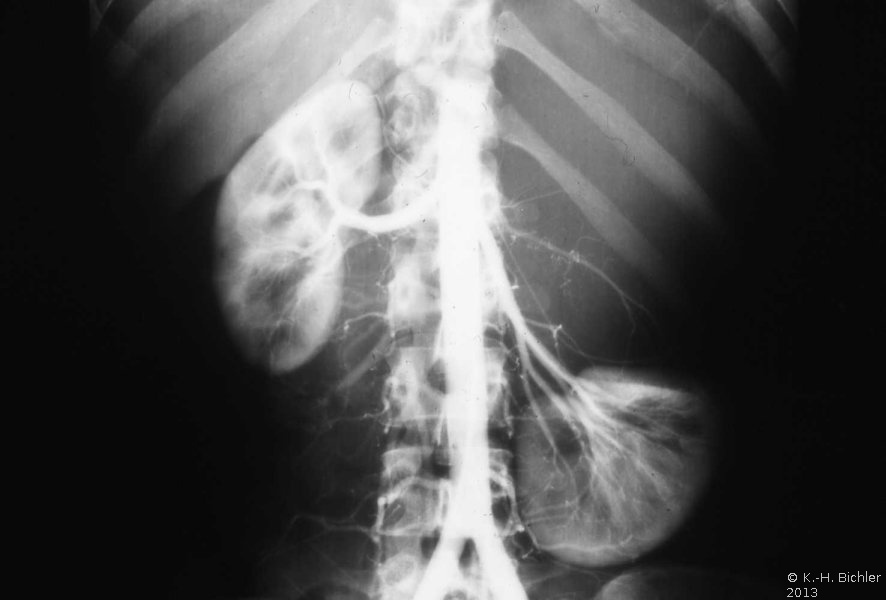

Differentialdiagnostisch muss auch an Zysten der Nebenniere gedacht werden, die zum Teil von erheblicher Größe sein können. Operative (laparoskopische) Entfernung ist bei großen, rupturgefähredeten Zysten angezeigt. Die Abbildungen dazu beispielhaft (Abbildungen 2,3).

In einem weiteren Beispiel fand sich eine 8x10 cm große Nebennierenzyste, die in der Angiographie eine deutliche Abdrängung der rechten Niere zeigt